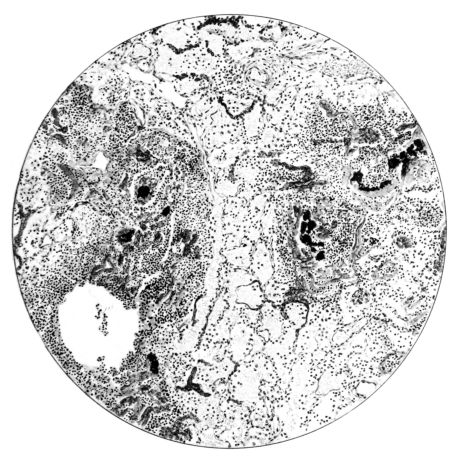

FIG. VII. AUTOPSY NO. 94. A NECROTIZING PROCESS LIKE THAT OF THE TRACHEA ILLUSTRATED IN FIGURE II. HERE IT IS SHOWN TO INVOLVE THE WALL OF THE BRONCHIOLE.

15There is considerable evidence to support the view that the disease spreads from bronchus to bronchus, and in keeping with this view, various stages in the inflammatory processes are more readily determined in these smaller structures than in the trachea. Furthermore, it must be emphasized that even the mildest and the most extreme of these stages are not infrequently encountered in the same lung. The earliest lesion is manifested by an increased homogeneity of the protoplasm of the epithelial lining of the bronchus. The cell protoplasm loses its normal granulation and the nucleus, somewhat darker than usual, becomes conspicuous on a red base (Fig. V). In the lumen of such a tube a serous exudate, perhaps mixed with mucus, is encountered, and there is some spreading apart of the surrounding muscular tissue with engorgement of the vessels. This picture merges gradually into one where the epithelium appears as a homogeneous, red-staining ribbon, devoid of nuclei, often exfoliated, in part at least, from the underlying submucosa (92). The change is traceable through the larger bronchi, even to the ducti alveolares, and not infrequently, bacteria, either as a diffuse, minute dotting or in the form of circumscribed, colony-like formations, are spread through the red, ribbon-like strand (Fig. XVI). With the exfoliation of the epithelial lining, the submucous vessels become more and more conspicuous and may bulge into the lumen of the tube (Fig. VI). That they actually weep into the lumen is proved by the presence of red blood cells in the exudate, now rich in mucus, broken-down nuclei, and desquamated cells. The necrotizing process may not extend deeper than the epithelial lining as is the status described above (140, 162), but it also frequently involves the underlying submucous and muscular layers, so that these lose their identity and stand out as homogeneous masses, in which fragmented nuclei and bacterial accumulations are prominent. Such deeper necrotizing areas may be focal (Fig. VII), or may involve the entire circumference of the tube (Fig. VIII). Occasionally, the epithelium, now dead and staining homogeneously, is lifted from the underlying submucosa in the form of a blister (66), and has very much the same appearance as the well known, early reaction which follows the application of croton oil to the rabbit’s ear. Where this occurs, the submucosa is less involved, as though the necrotizing agent had not penetrated to the same depth and the serous reaction beneath were actually a beneficent exudate. These blisters are in contrast with the deeper areas where the fibrinous mass, mixed with the dead tissue, forms an intensely staining ring or band, which extends through the bronchiolar wall even to the surrounding alveoli.